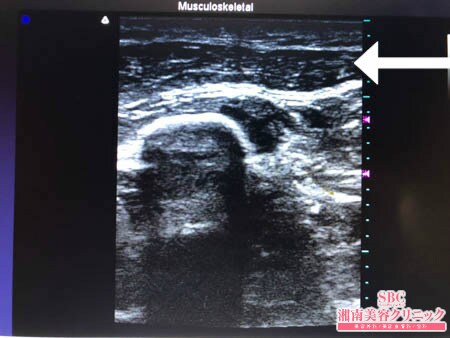

No.205601【脂肪吸引】【動画あり】湘南美容外科脂肪吸引最高責任者である竹田先生による脂肪吸引のフォトギャラリー!中国在住の細い二の腕の患者様の二の腕の脂肪吸引!術中3Dタッチビュー・右二の腕

硬くて線維質だった皮下脂肪。

非常に脂肪吸引しにくい状態でしたが

徹底的に根こそいでおきましたので

患者様にはご満足いただけることでしょう。